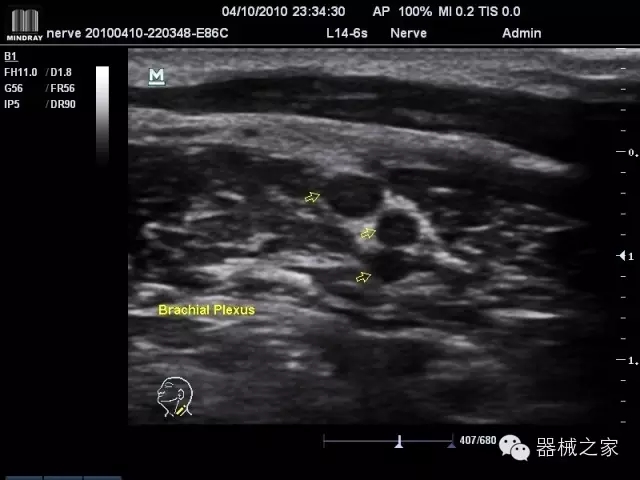

經(jīng)典產(chǎn)品:M7(星鉆)

臨床圖片賞析

·優(yōu)秀的圖像效果、強(qiáng)大的功能體驗(yàn)、豐富的探頭選擇、合理的便攜式設(shè)計(jì),全中文顯示及病人管理界面,使得M7在任何場(chǎng)合、任何時(shí)候都能快速響應(yīng)更好的心血管、腹部、婦產(chǎn)、小器官等常規(guī)超聲檢查以及肌骨、神經(jīng)、顱腦、術(shù)中等新興領(lǐng)域的使用需求;